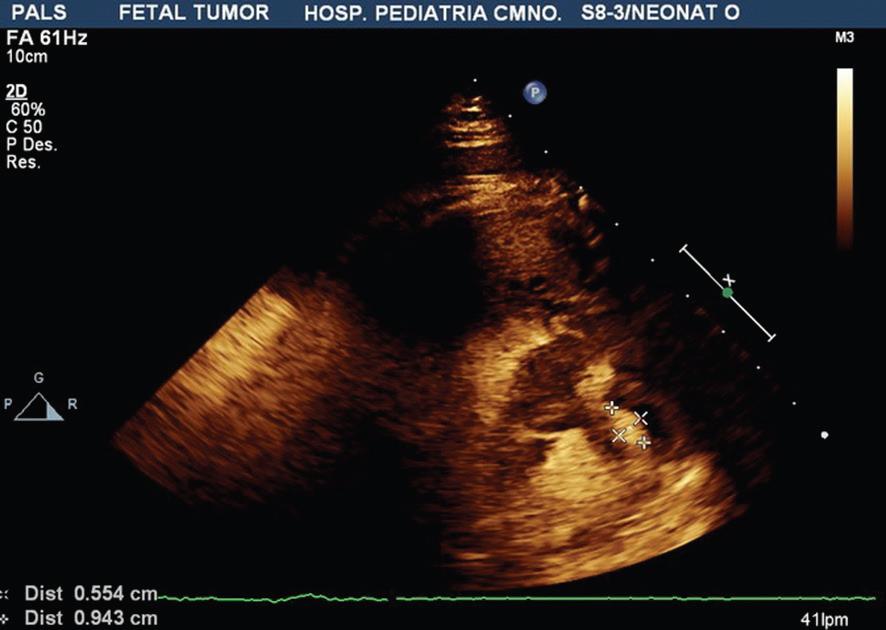

- El primer caso se trata de una paciente de 20 años de edad, sin antecedentes heredofamiliares de importancia, la cual inicia control de embarazo de alto riesgo en tercer nivel por múltiples amenazas de aborto. Derivada a nuestro hospital a las 36 semanas de gestación, realizándose el primer ecocardiograma prenatal por parte de nuestro servicio detectando tumores cardiacos compatibles con rabdomiomas, con imagen ecogénica en aurícula derecha de 18 mm y en ventrículo derecho de 20 mm con septum interventricular de 8 mm (Fig. 1), sin datos de obstrucción al tracto de salida, por lo que se decide continuar con el embarazo. Nace por cesárea, sin complicaciones. Se realiza ecocardiograma posnatal de control con los hallazgos previos, reportando tumoración a nivel de la cava superior de 13 x 18 mm, tumoración en surco atrioventricular de 15.4 x 4.5 mm, en ventrículo derecho con tumoración de 17.4 x 22 mm, siendo bilobulado, a nivel del ventrículo izquierdo con múltiples tumoraciones adheridas al septum y a la pared anterior la mayor de 7.7 x 8.2 mm (Fig. 2), corroboradas por resonancia magnética (Fig. 3). Debido a la asociación de tumores intracardiacos con esclerosis tuberosa fue valorado por el Servicio de Neurología, en donde mediante la realización de resonancia magnética de encéfalo se evidencia lesión nodular intraaxial en el giro recto derecho y nódulos subependimarios en ambos ventrículos laterales (Fig. 4), con hallazgos referidos que se encuentran dentro del espectro de esclerosis tuberosa. Se mantiene en vigilancia, en control por la consulta externa de dicho servicio.

Figura 1 Imagen del ecocardiograma fetal donde se observa en cuatro cámaras 2D imagen de tumor en ventrículo derecho de 20 mm con septum interventricular de 8 mm.